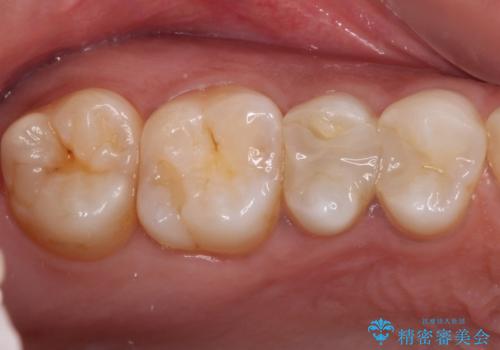

- 奥歯にフロスが引っかかるようになり、虫歯ではないかとのことで来院された患者様です。

レントゲン写真より、左右奥歯にむし歯があることが分かりました。

奥で目立たないことから、虫歯の再発リスクが最も低く、咬合力による歯への負担も少ないゴールドインレー(PGAインレー、白金加金インレー)にて修復治療をすることとしました。